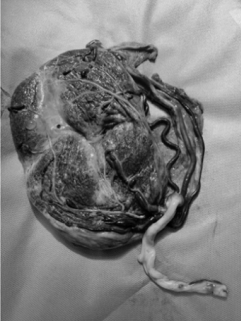

Uma secundigesta, com um parto normal anterior e idade gestacional de 36 semanas e dois dias, deu entrada no pronto-atendimento obstétrico com queixa de sangramento vaginal em grande quantidade há quarenta minutos. Refere que a hemorragia ocorreu “do nada”, tendo início após um “acesso de tosse”. Nega dor abdominal. Realizou seis consultas de pré-natal, com todos os exames dentro do limite da normalidade. Nega antecedentes pessoais de comorbidades. Ao exame de entrada, descorada +/4+, PA de 90 x 50 mmHg, FC de 101 bpm, altura uterina de 33 cm, ausência de dinâmica uterina, tônus uterino normal e BCF de 101 bpm. Especular mostrando grande quantidade de coágulos na vagina e sangramento ativo por orifício externo do colo. Foi encaminhada para cesariana de emergência. A foto abaixo corresponde à placenta, após dequitada.

Com base nesse caso hipotético, assinale a alternativa que apresenta o diagnóstico do sangramento da segunda metade da gestação.